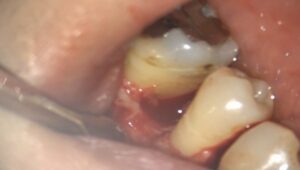

実際の治療の様子を見てみましょう。

歯ぐきには慢性的な炎症があり、骨は平坦に溶けています。

ここに深い歯周ポケットがあります。

まずは衛生士さんによるクリーニングを進め、取れる部分のプラークや歯石を取ります。

その後、深い歯周ポケット内に潜んでいる歯石を歯周外科治療によって取るのです。

手術の時の写真です。

これは、マイクロスコープで撮影している動画を一部切り取ったものです。

歯ぐきを開いて見てみると、その下の骨は溶けてなくなっているのがわかると思います。

手術では、歯の根元の深いところについている歯石を取り、根の表面を滑沢にしていきます。